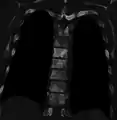

- Sclerosis of the bones of the thoracic spine due to prostate cancer metastases (CT image)